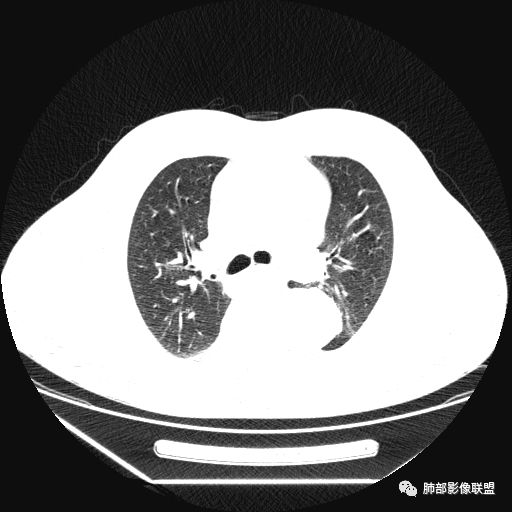

曹志勇:右肺尖后段类圆形病灶,边界清边,缘锐利,宽基底与胸膜相连,环形强化,内似见蛇纹血管征,考虑胸膜孤立性纤维瘤,右肺外底段病灶,考虑炎性可能大

张帅:患者中年男性,咳嗽 咳痰3月,痰为白色粘痰,左上肺病灶,边缘光滑,周围未见毛刺 分叶,肺组织受挤压,与胸膜关系密切,部分层面与胸膜脂肪间隙消失,有胸膜尾征,病灶定位于胸膜,病灶增强可见强化,边缘可见增强血管,内可见低密度区,考虑 孤立胸膜纤维瘤?神经鞘瘤?右肺下叶外基底段病灶,病灶与胸膜有牵拉,病灶边缘光滑,平直 u型征,未见明显毛刺,增强病灶内可见增强血管影,边缘低密度,考虑病灶内存在痰栓。右下肺病灶考虑良性炎症性病灶,ABPA?

薏米:左下近脊柱旁可见一结节状密度增高影,肺外,边界清,边缘规整,无分叶,无毛刺,无棘突,宽基底与胸膜相连,不均匀轻度强化,考虑为良性病变,神经源性可能性大,为神经鞘瘤,鉴别孤立性神经纤维瘤,神经节瘤,右肺片装密度增高影,考虑为炎症可能性大

右叶下叶病变,顺支气管走形成不规则片样,考虑炎性

Shelia??:左下胸腔脊柱旁类圆形软组织肿块影,呈D字证,可见胸膜掀起,邻近肺组织受压呈弧形致密影改变,增强后似轻度均匀强化,邻近骨质未见明显异常,考虑良性病变,孤立性纤维瘤?鉴别神经源性肿瘤另外右肺小叶不规则病灶,边缘平直收缩为主,局部可见弓形凹陷,密度均匀,增强后轻中度均匀强化,周围肺野尚清晰,考虑炎性肉芽肿病变,OP?但是感觉周围太光整,还是就是慢性炎症?

田园晚风:左胸后部近胸椎占位,密度均匀,边缘光滑,呈d字征,外侧可见压缩肺组织,右肺见条状致密影,与支气管走行一致,考虑左侧神经源性肿瘤,右肺abpa?

张小兵:老年男性,慢性病程,咳嗽咳痰3月,左下肺脊椎旁沟区见宽基底类圆形软组织肿块,无分叶,瘤肺境界光整,其内见点状钙化,周边肺组织挤压,胸膜尾征,延迟强化,提示内含纤维成分,考虑神经源性肿瘤,SFT可能。右下肺病灶收缩力强,内见扩张支气管,提示慢性炎症,考虑机化。

另外右肺病变,平直收缩,应该与左边病变二元,目前感觉炎症,强化均匀